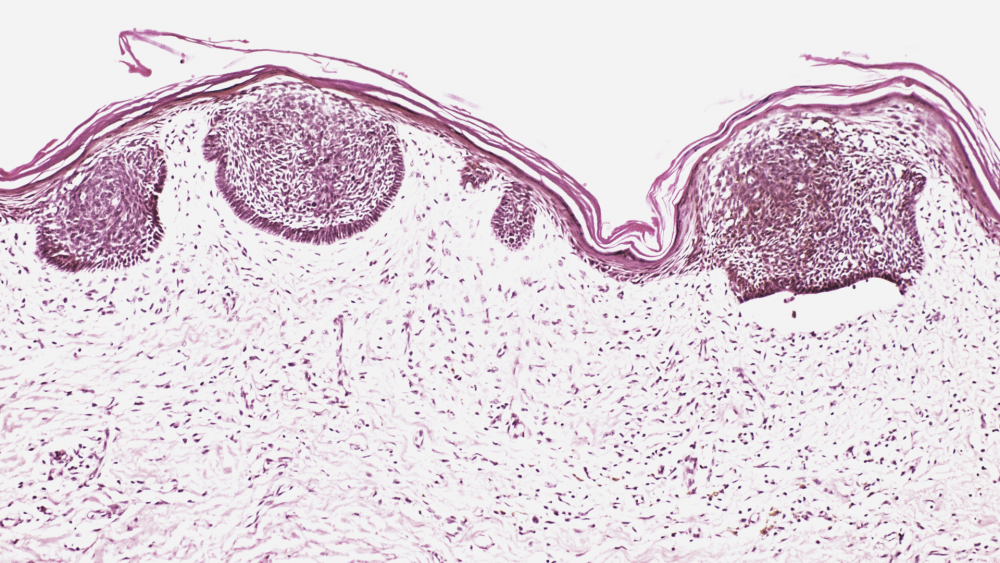

Рак кожи: базалиома

Рак кожи — собирательное название для злокачественных новообразований, сформировавшихся из трансформировавшихся клеток кожи. К раку кожи относятся различные виды заболеваний, основные из них — базальноклеточная карцинома и сквамозноклеточная карцинома.